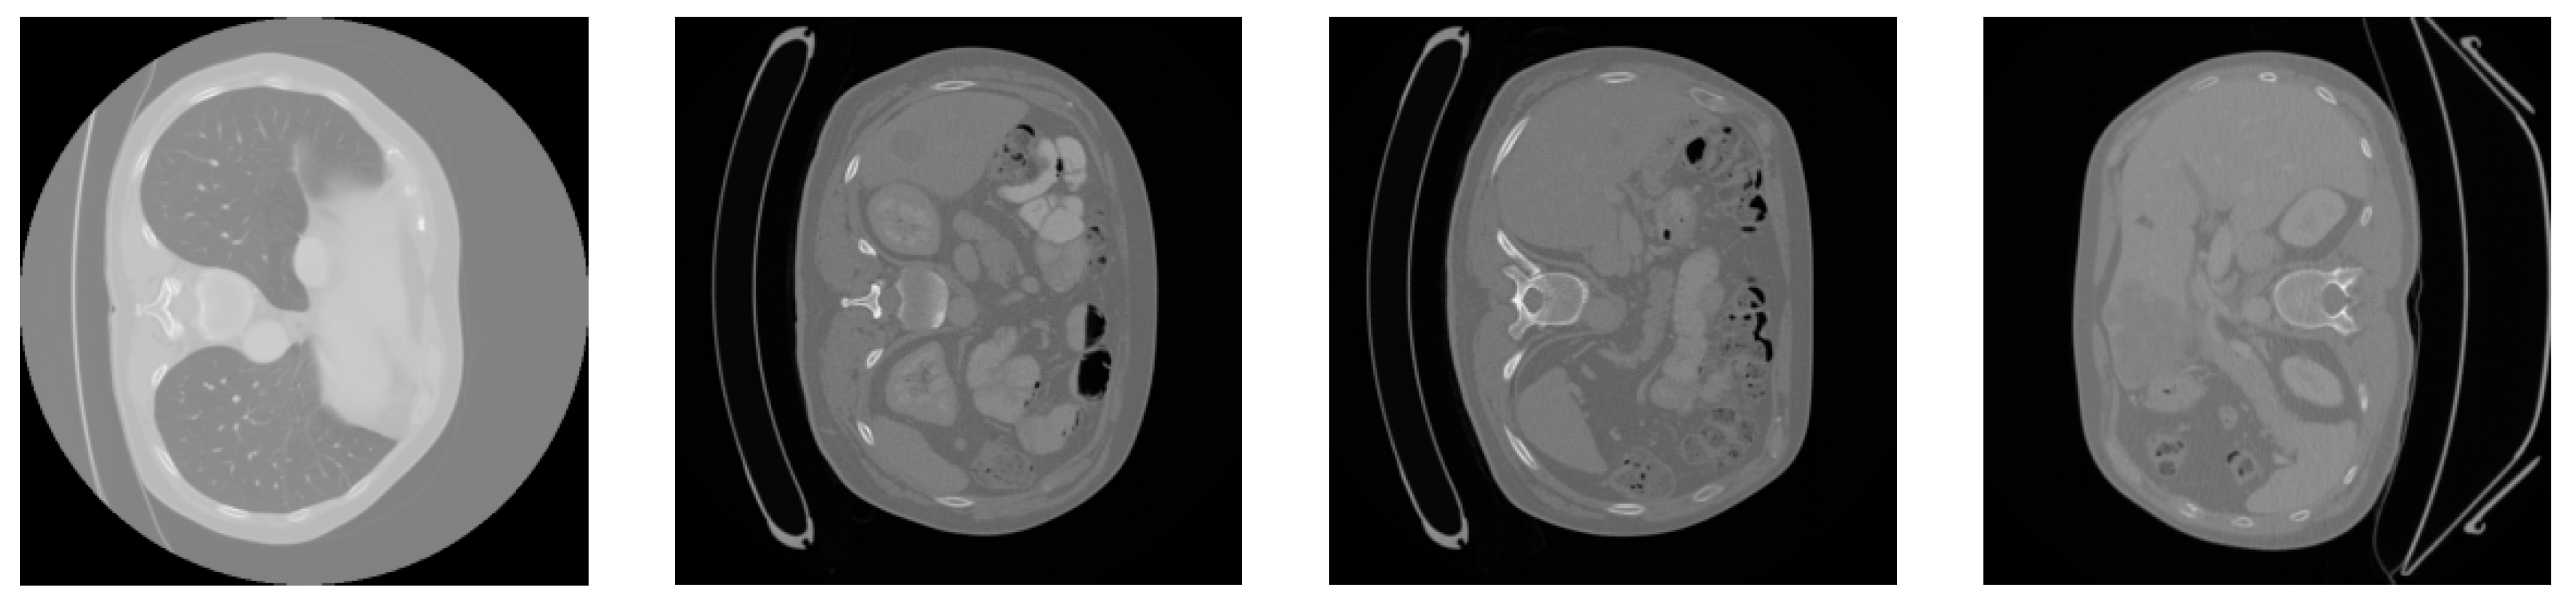

5.1. Dataset

5.2. Data Preprocessing